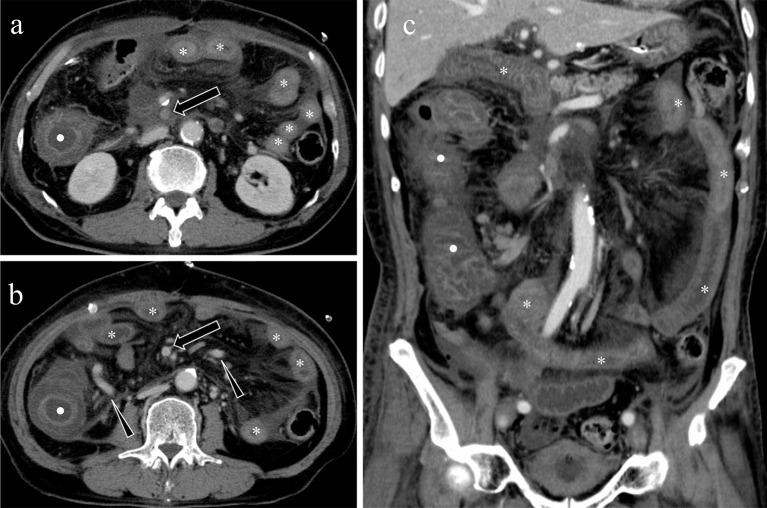

Acute mesenteric ischemia is a life-threatening condition. A comprehensive approach involving a multidisciplinary team to review patient background, clinical history, physical examination, laboratory data, and imaging examination for respective diagnosis of superior mesenteric arterial occlusion, nonocclusive mesenteric ischemia, and superior mesenteric venous occlusion is essential. The most important imaging modality is computed tomography, which is used for diagnosis and for directing therapeutic strategy (e.g., endovascular revascularization, surgical bowel resection, or conservative management). Computed tomography image findings can support triaging of irreversible transmural bowel necrosis compared with reversible ischemic change with reperfusion. In this review article, the computed tomography imaging findings specifically associated with the pathophysiology of superior mesenteric arterial occlusion, nonocclusive mesenteric ischemia, and superior mesenteric venous occlusion are reviewed.

急性肠系膜缺血是一种危及生命的疾病。采用多学科团队的综合方法来审查患者背景、临床病史、体格检查、实验室数据以及影像学检查,以分别诊断肠系膜上动脉闭塞、非闭塞性肠系膜缺血和肠系膜上静脉闭塞至关重要。最重要的影像学检查方法是计算机断层扫描,它用于诊断并指导治疗策略(如血管内血运重建、手术肠切除或保守治疗)。计算机断层扫描图像结果有助于区分不可逆的透壁性肠坏死与可通过再灌注逆转的缺血性改变。在这篇综述文章中,将对与肠系膜上动脉闭塞、非闭塞性肠系膜缺血和肠系膜上静脉闭塞的病理生理学具体相关的计算机断层扫描影像学结果进行综述。